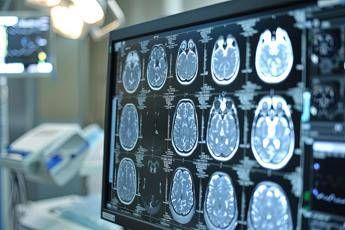

(Adnkronos) – Una volta erano considerate delle neoplasie rare, ma oggi i gliomi sono sempre più diffusi. In Italia i casi annui ammontano a oltre 3mila e corrispondono al 40% di tutti i tumori cerebrali primitivi. Tra i gliomi, quelli di basso grado di frequenza più rara rappresentano una sfida clinica rilevante anche per la loro evoluzione e l'assenza di trattamenti mirati, oltre alla resistenza che dimostrano ai trattamenti convenzionali. Sono malattie orfane di cui si parla poco anche fra i clinici, tra le istituzioni e sui media. Perciò la Fondazione Aiom (Associazione italiana di oncologia medica) ha lanciato nei mesi scorsi 'I gliomi', una campagna nazionale online di formazione e informazione. Sono stati organizzati webinar rivolti agli oncologi medici e alle altre figure sanitarie coinvolte nel team multidisciplinare. Sono stati indirizzati a pazienti e caregiver ulteriori eventi online insieme a un'attività di sensibilizzazione sui principali social media. I risultati dell'iniziativa sono presentati oggi in una conferenza stampa virtuale promossa da Fondazione Aiom. Il progetto è stato realizzato con il contributo non condizionante del Gruppo Servier in Italia. "Sono tumori cerebrali molto complessi e che spesso vengono diagnosticati in età giovanile – afferma Saverio Cinieri, presidente di Fondazione Aiom – Si sviluppano da cellule del cervello chiamate gliali e possono avere una prognosi variabile, ma potenzialmente a lungo termine. La gestione della patologia richiede una stretta collaborazione fra neurochirurgo, radioterapista e oncologo medico. Attraverso il bisturi è possibile rescindere la massa tumorale oppure eseguire una biopsia grazie a nuove e sofisticate tecnologie. La radioterapia permette di ridurre il rischio di recidiva o eliminare quella parte di cancro che non è stato possibile rimuovere chirurgicamente. Viene somministrata insieme alla chemioterapia e le sedute sono di solito diluite nel corso del tempo, per limitare l'impatto degli effetti collaterali. Infine, l'oncologo medico deve scegliere i farmaci da somministrare e deve selezionarli valutando le condizioni cliniche del singolo paziente". "Anche per il trattamento dei gliomi, in particolare quelli di basso grado, si può ricorrere all'oncologia di precisione che potrà ridisegnare la pratica clinica nel prossimo futuro – illustra Enrico Franceschi, direttore dell'Oncologia del sistema nervoso all'Irccs Istituto delle scienze neurologiche di Bologna – E' molto importante verificare la presenza o meno delle mutazioni Idh1 e Idh2. Questi biomarcatori indicano specifiche patologie caratterizzate da una prognosi decisamente più favorevole e maggiore sensibilità dei gliomi alla radio e chemioterapia. Al momento della diagnosi è quindi essenziale l'esecuzione precoce di alcuni test molecolari per identificare al meglio i diversi sottotipi di gliomi. Tra le terapie di nuova generazione vi è anche vorasidenib, un farmaco orale inibitore Idh1 e Idh2 che ha dimostrato di essere un trattamento efficace nel posticipare la radio e chemioterapia nei gliomi di basso grado ed è una rilevante innovazione medico-scientifica". "Come tutti i tumori cerebrali – prosegue Cinieri – anche i gliomi di basso grado hanno un forte impatto sulla vita del paziente. Sono tante le complicanze che possono verificarsi durante l'intero percorso di cura, perché intervenire sul cervello umano con radiazioni ionizzanti o con interventi chirurgici può comprometterne alcune funzioni basilari. Tra queste vi sono le capacità di parlare o di movimento. Si rendono a volte necessari interventi riabilitativi di logopedisti, fisioterapisti o altri professionisti come lo psiconcologo. Ricevere la notizia della presenza di un tumore in una zona così particolare e delicata porta quasi sempre a depressione e ansia, soprattutto quando il primo approccio è un periodo di osservazione privo di un trattamento attivo. Le terapie innovative sono in grado di prolungare in modo significativo la sopravvivenza libera da progressione e garantiscono un buon profilo di sicurezza e tollerabilità". "Ancora una volta l'oncologia medica è centrale nella gestione multidisciplinare di neoplasie estremamente complesse ed insidiose – sottolinea Franceschi – Il trattamento dei gliomi inizia nel momento della diagnosi che deve essere sia morfologica che molecolare. Esistono infatti 150 diversi sottotipi di neoplasia cerebrale ed è fondamentale riconoscere fin da subito le caratteristiche del singolo caso per poter così selezionare le terapie più appropriate. Fino a pochi anni fa avevamo a disposizione solo chirurgia, radioterapia e chemioterapia. Ora i farmaci ad azione mirata sono una realtà anche nella cura dei tumori cerebrali che esprimano specifiche alterazioni molecolari". "Nasce da questo rapido progresso nei trattamenti la nostra campagna d'informazione rivolta principalmente a specialisti clinici e pazienti – conclude Cinieri – L'oncologia medica è in costante evoluzione ed è compito di associazioni e fondazioni garantire sempre un aggiornamento scientifico qualificato. L'oncologia di precisione è una realtà consolidata in molte forme di cancro ed è un approccio che indirizza sempre più le nostre scelte terapeutiche. Sta portando a risultati davvero interessanti ed inimmaginabili fino a pochi anni fa anche per neoplasie rare e difficili da trattare come i gliomi di basso grado Idh mutati".